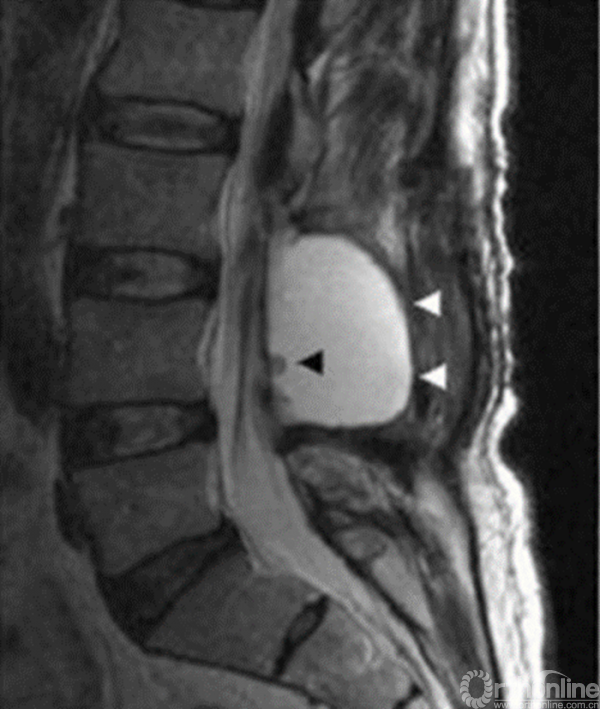

假性硬膜外膨出1

1. D. L. Marinus Oterdoom, Rob J. M. Groen, Maarten H. Copes. Cauda equina entrapment in a pseudomeningocele after lumbar Schwannoma extirpation[J].Eur Spine J 2010;19: 158–161.